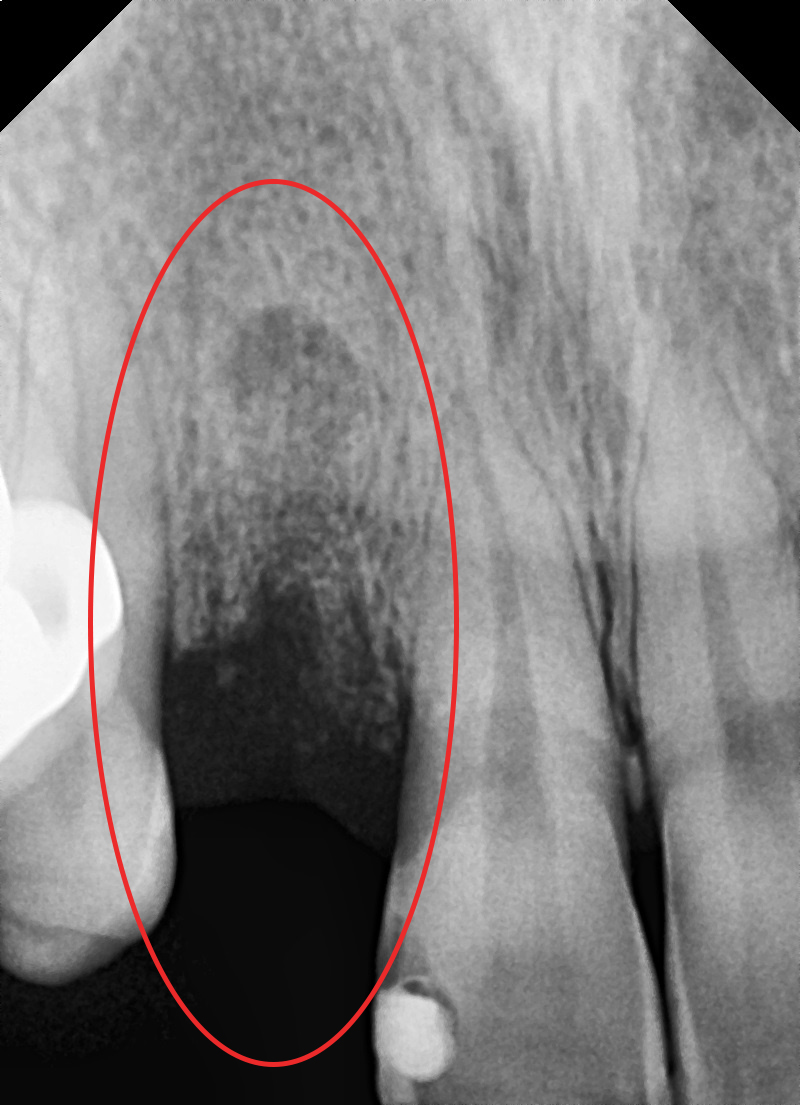

1. 치관 파절, 뿌리 끝 염증(Apical lesion) 발견

2. 잔존치근 발거

3. 발치와보존술 시행

4. 발치와보존술 후, 고정체 식립 및

인비절라인 치아교정 치료 시작